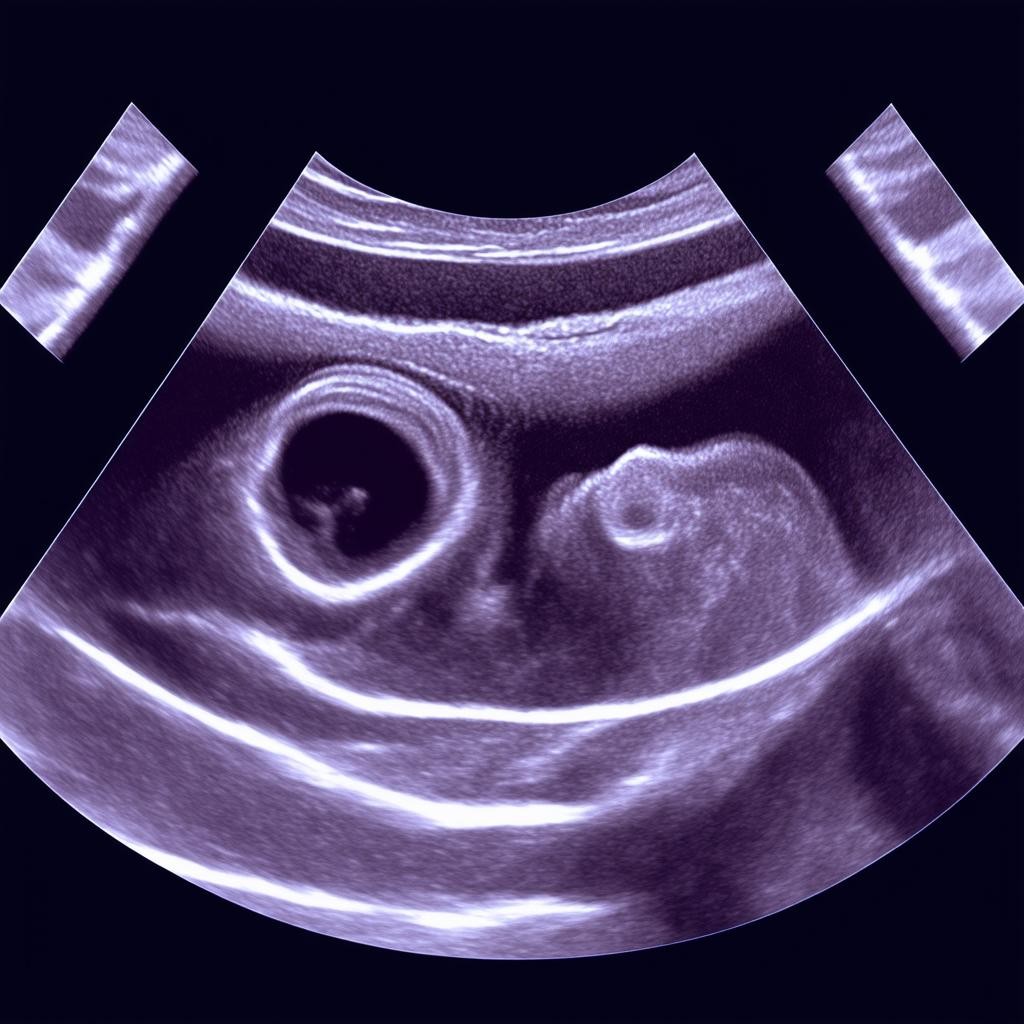

УЗИ молочных желез представляет собой один из наиболее информативных и безопасных методов диагностики, который позволяет выявить различные патологии на ранних стадиях. Этот метод основан на использовании высокочастотных звуковых волн, которые создают детальное изображение внутренней структуры молочных желез. В отличие от маммографии, ультразвуковое исследование не использует ионизирующее излучение, что делает его абсолютно безопасным для пациенток любого возраста, включая беременных и кормящих женщин. Современное оборудование обеспечивает высокую точность диагностики, позволяя обнаруживать даже минимальные изменения в тканях.

Современное ультразвуковое оборудование позволяет выявлять широкий спектр патологических изменений. Диагност оценивает структуру тканей, наличие образований, их размеры, форму, контуры и эхогенность. УЗИ эффективно обнаруживает кисты - заполненные жидкостью полости с четкими контурами. Метод прекрасно визуализирует фиброаденомы - доброкачественные опухоли, а также позволяет заподозрить злокачественные образования по характерным признакам: неровным контурам, неоднородной структуре, акустической тени. Допплерография оценивает васкуляризацию образований, что имеет важное диагностическое значение.